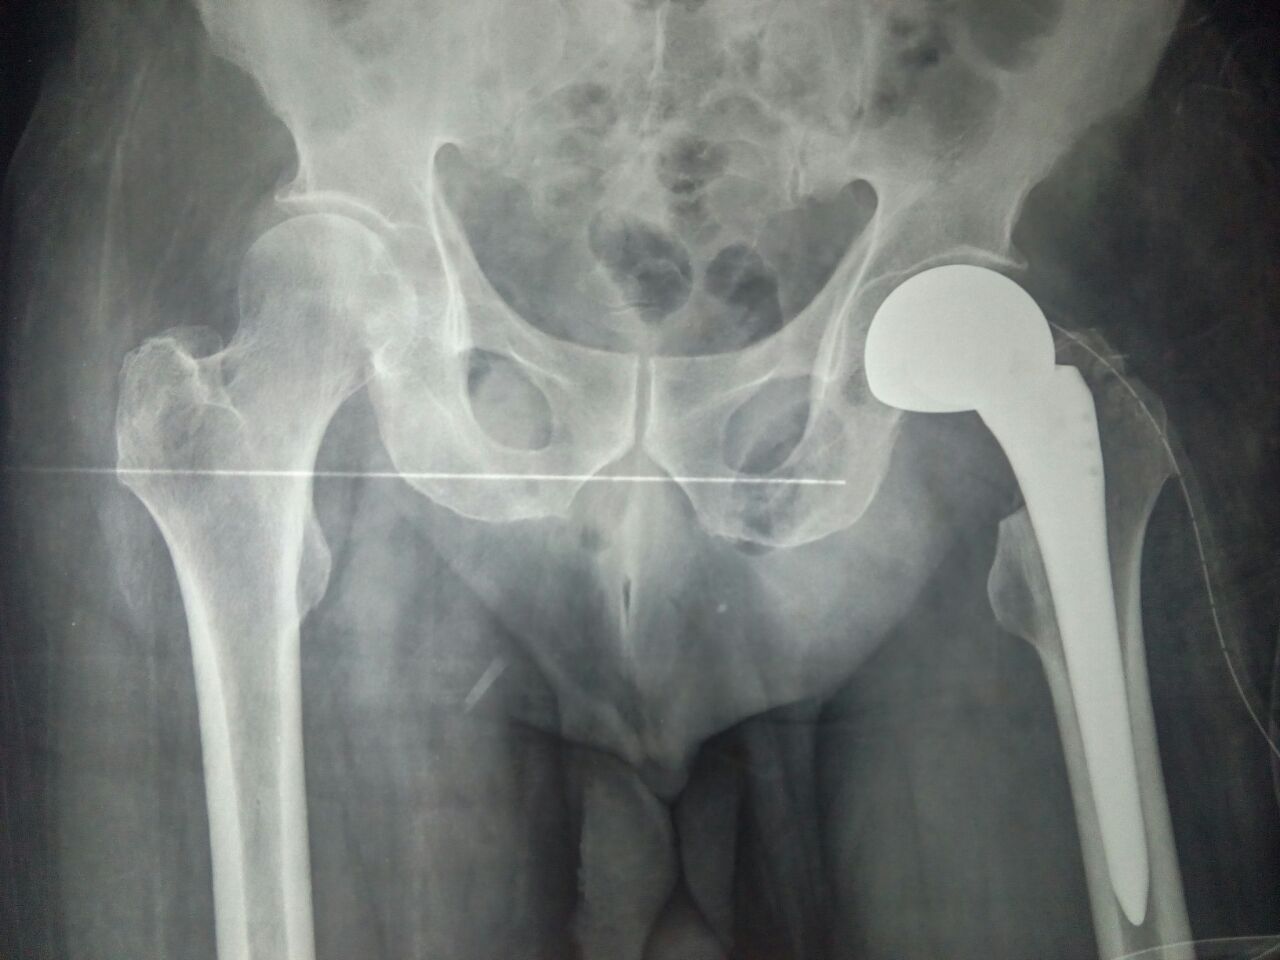

Post-Operation

Successful Comminuted Intertrochanteric Fracture - Surgery for an Old-Man

The Patient was 80 Years Old Man had fallen down unfortunately and got Comminuted Intertrochanteric Fracture .They approached Sooriya Hospital on 15th of July 2018 for the Treatment. The patient with so much of complications now been treated by Imported Bipolar Hemi Arthroplasty by the Doctor P.Sankaralingam (M.S (Ortho), DNB (Ortho), MNAMS) on 16.07.2018. The successful surgery made by our doctor, makes the patient to walk immediately the next day with full weight bearing walker.